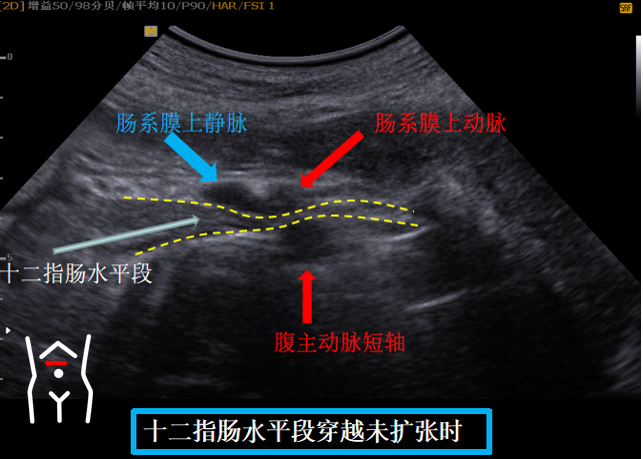

第五组切面

十二指肠水平段穿越肠系膜上动脉上静脉与腹主动脉间隙切面。